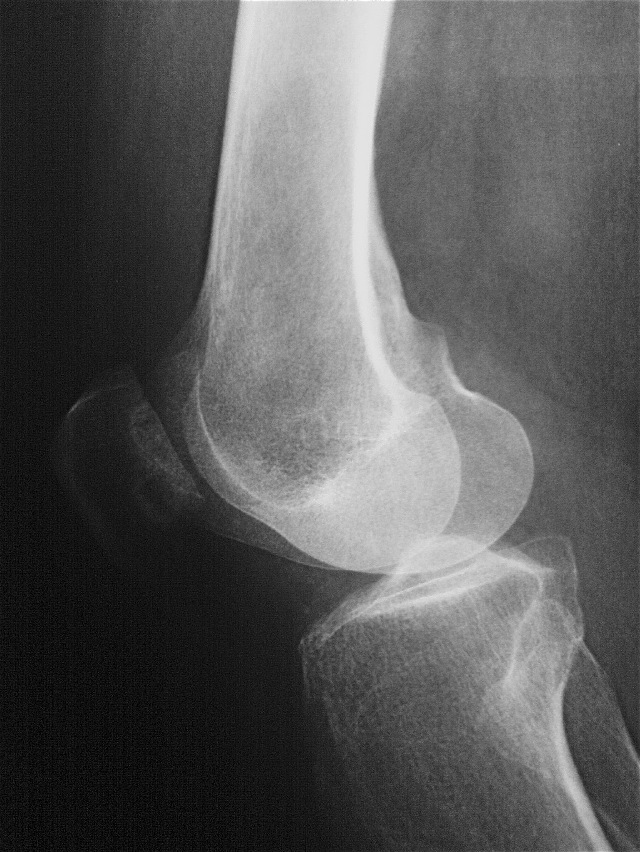

Врач проводит внешний осмотр, а с помощью пальпации выявляет вздутие и отечность тканей. Основные методы диагностики заболеваний коленного сустава включают:

- рентгенографию в осевой проекции (ноги сгибаются в коленях под углом 45°);

- компьютерную томографию (КТ) и магнитно-резонансную томографию (МРТ), которые помогают выявить изменения в положении надколенника (наклон или подвывих);

- артроскопию коленного сустава, применяемую при признаках артроза, для оценки степени тяжести заболевания.

| I стадия (мягкая) | Легкий дискомфорт в колене, особенно при длительной нагрузке или после отдыха; незначительный отек; щелчки в колене. | Рентгенограмма: без видимых изменений; МРТ: незначительное утончение хряща. |

| II стадия (умеренная) | Умеренная боль в колене, усиливающаяся при физической активности; отек может быть более выраженным; чувство нестабильности колена; боль при приседании. | Рентгенограмма: может быть незначительное уплощение суставной поверхности надколенника; МРТ: умеренное утончение хряща, возможно наличие небольших трещин. |

| III стадия (тяжелая) | Сильная боль в колене, ограничивающая физическую активность; выраженный отек; боль в покое; ощущение хруста или щелчков в колене; ограничение подвижности колена. | Рентгенограмма: уплощение и деформация суставной поверхности надколенника; МРТ: значительное утончение хряща, глубокие трещины, возможно наличие фрагментов хряща. |

| IV стадия (деструктивная) | Сильная постоянная боль; выраженный отек; значительное ограничение подвижности колена; деформация колена; возможно развитие артроза. | Рентгенограмма: выраженная деформация суставной поверхности надколенника, признаки артроза; МРТ: полное разрушение хряща, субхондральный склероз. |